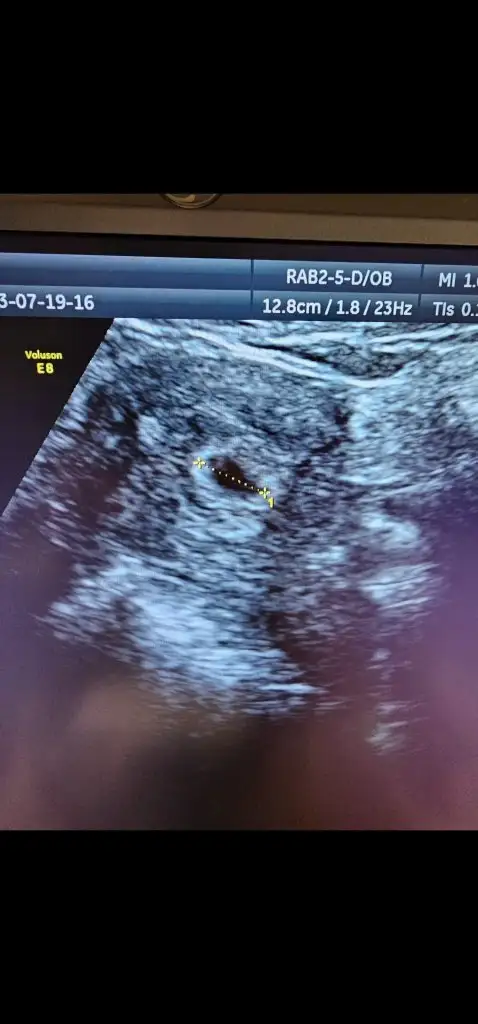

Bizde salı günü gittik sana yazmayı unuttum heycandanMerhaba hanımlar, dün akşam biraz kanamam oldu alelacele doktora gittik o sıra keseyi de görmüş olduk çok şükür. Biraz riskli geçiyor gebeliğim. Normal mi bu sizce. Bir de cinsiyet için çok erken ama sizce kese neye benziyor

Ayyy çok sevindim, çok güzel bir haber bu. Rabbım kucağımıza almayı nasip etsin inşallahBizde salı günü gittik sana yazmayı unuttum heycandan6+1 di Salı günü ve keseyi gördük kalp atışını duyduk çok şükür ben keseden cinsyeti pek anlamam açıkçası keseyi görmene çok sevındım daha da sağlıklı haberler alırız inşallah